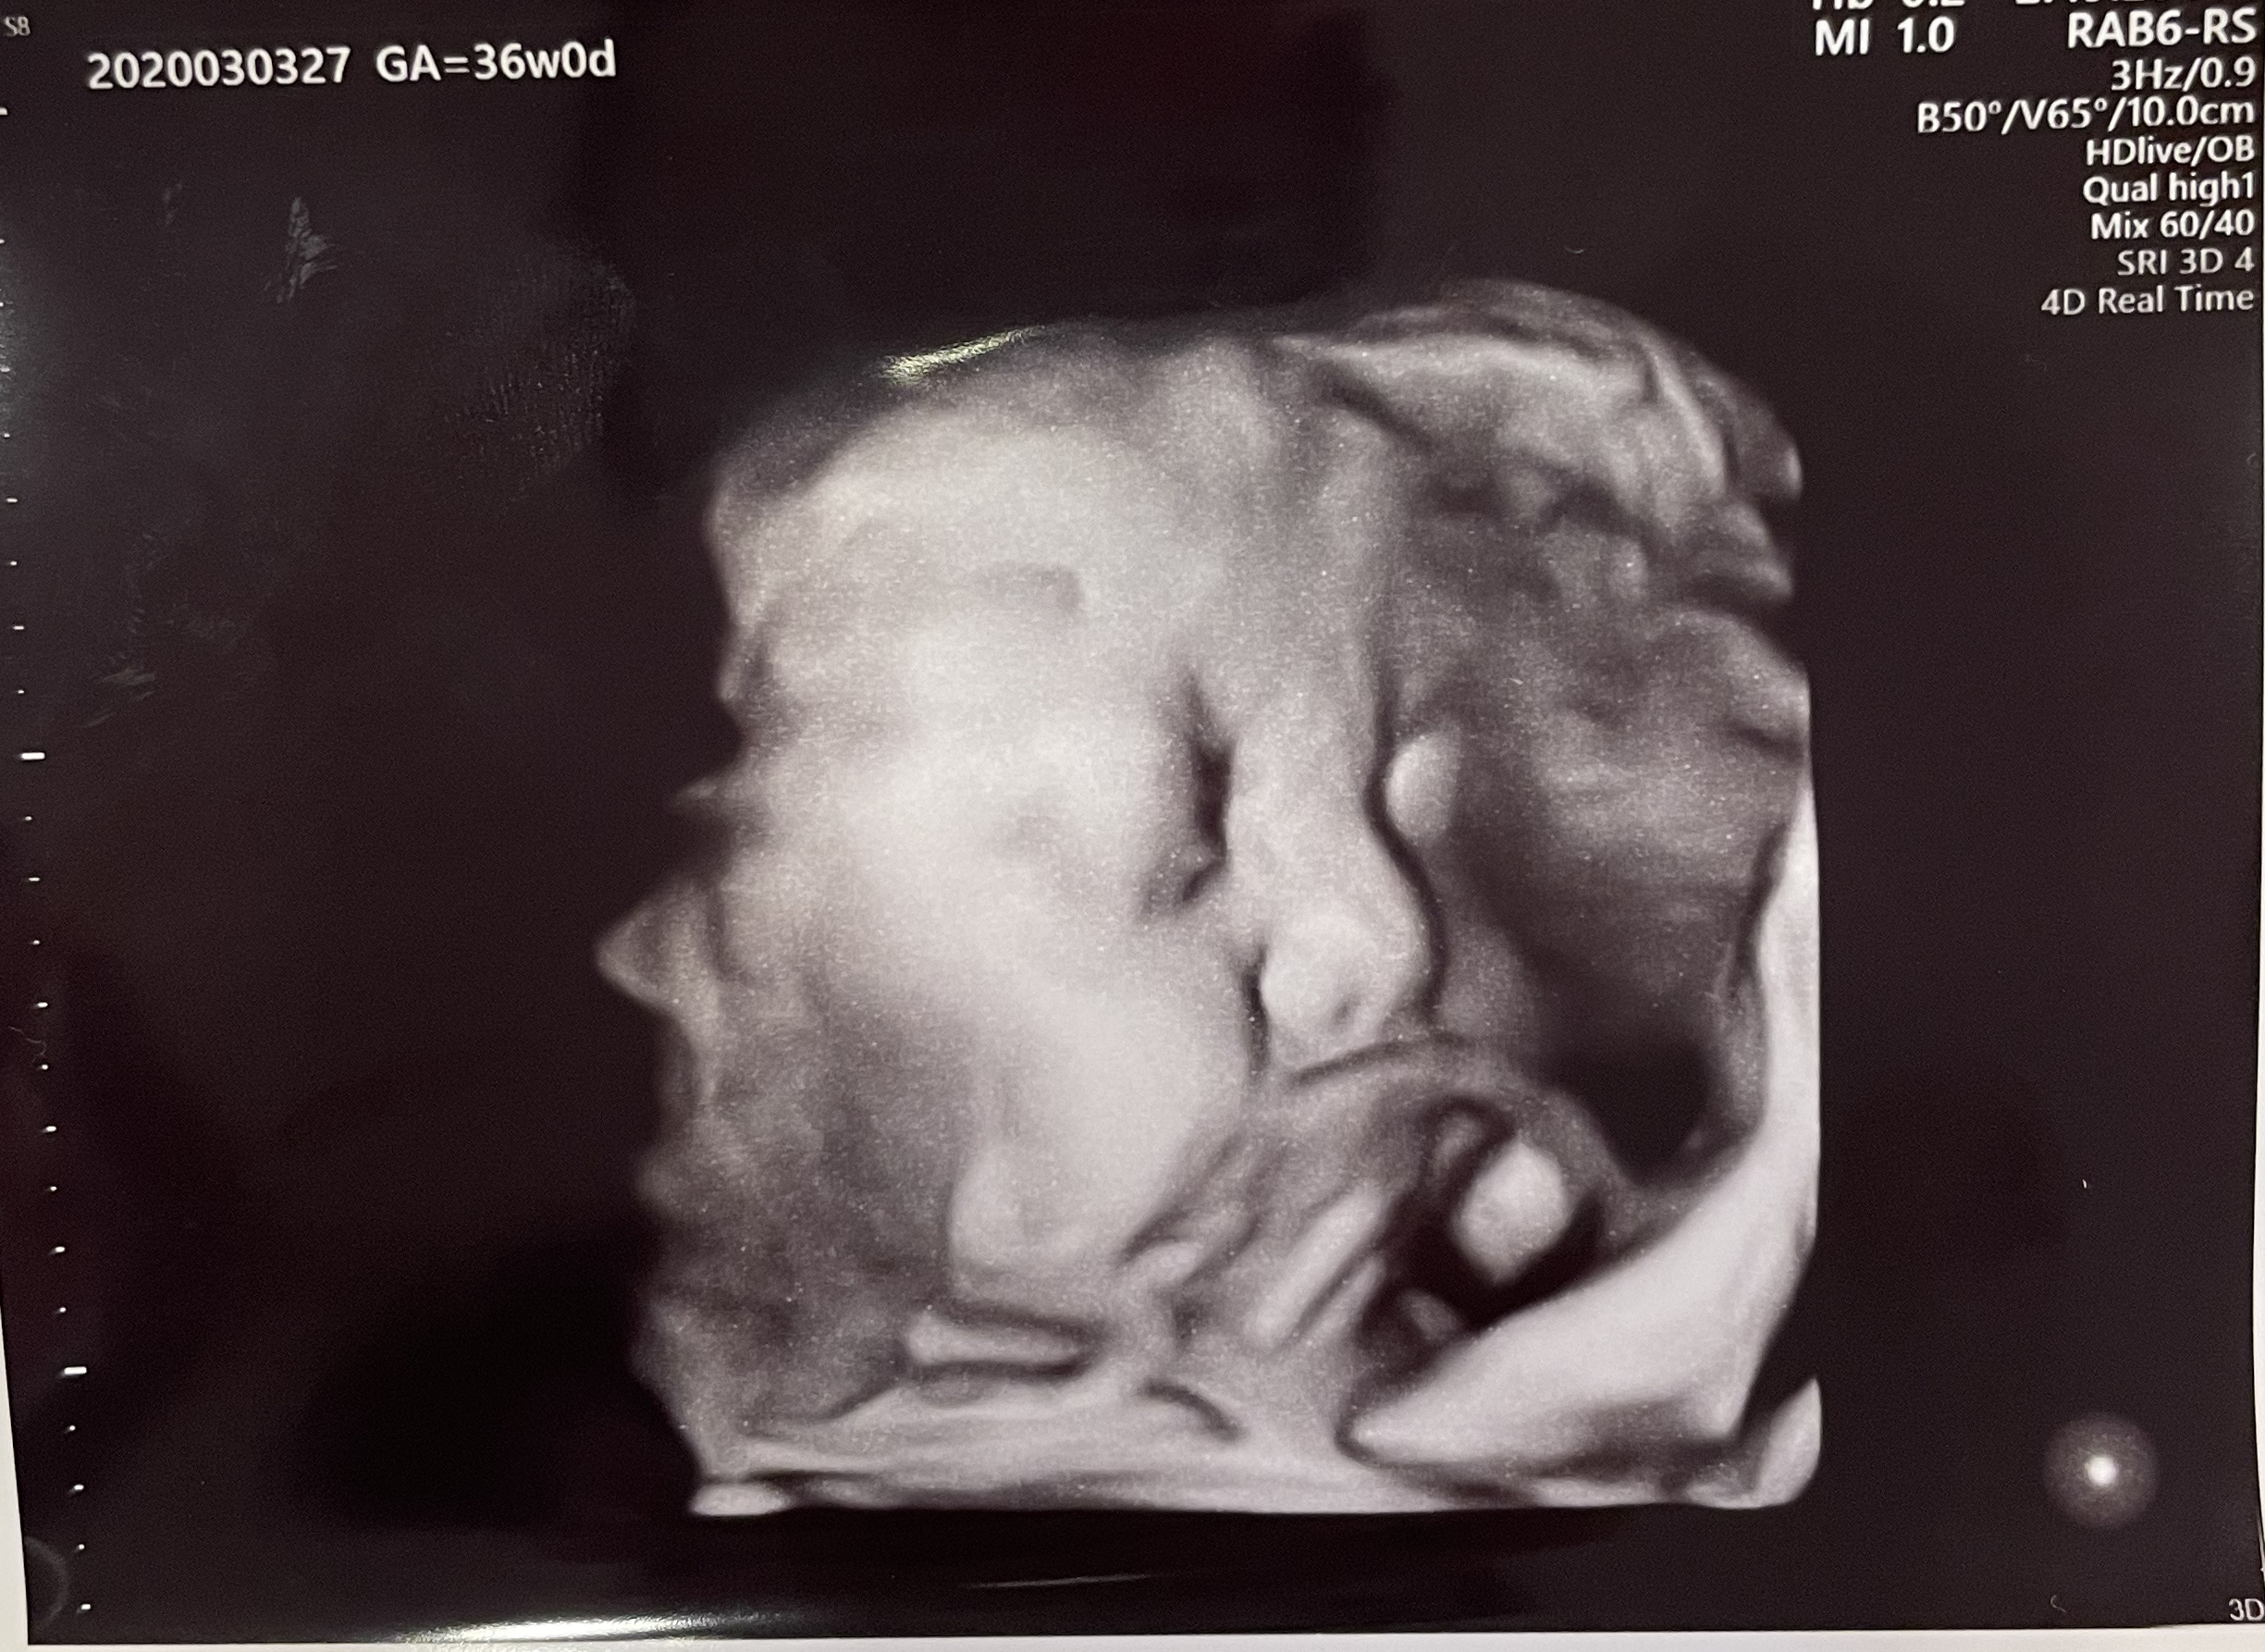

赤ちゃんの4Dエコー、だいぶリアルに感じられてきました。ほっぺもぷっくりしてきて、鼻も鼻の穴もしっかり見えます。臍の緒をちゅーちゅー吸って、母乳を飲む練習をしているみたいです😍

今更ですが育良クリニックの先生は、赤ちゃんのエコー写真を撮るのがすごく上手だと思います。

基本的に経腹エコーをするときはデフォルトで4Dエコーを撮るからなのか、いつもお顔をきれいにうつしてくれます。